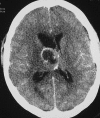

This pictorial review is based on our experience of the follow-up of 120 patients at our multidisciplinary center for hereditary hemorrhagic telangiectasia (HHT). Rendu-Osler-Weber disease or HHT is a multiorgan autosomal dominant disorder with high penetrance, characterized by epistaxis, mucocutaneous telangiectasis, and visceral arteriovenous malformations (AVMs). The research on gene mutations is fundamental and family screening by clinical examination, chest X-ray, research of pulmonary shunting, and abdominal color Doppler sonography is absolutely necessary. The angioarchitecture of pulmonary AVMs can be studied by unenhanced multidetector computed tomography; however, all other explorations of liver, digestive bowels, or brain require administration of contrast media. Magnetic resonance angiography is helpful for central nervous system screening, in particular for the spinal cord, but also for pulmonary, hepatic, and pelvic AVMs. Knowledge of the multiorgan involvement of HHT, mechanism of complications, and radiologic findings is fundamental for the correct management of these patients.